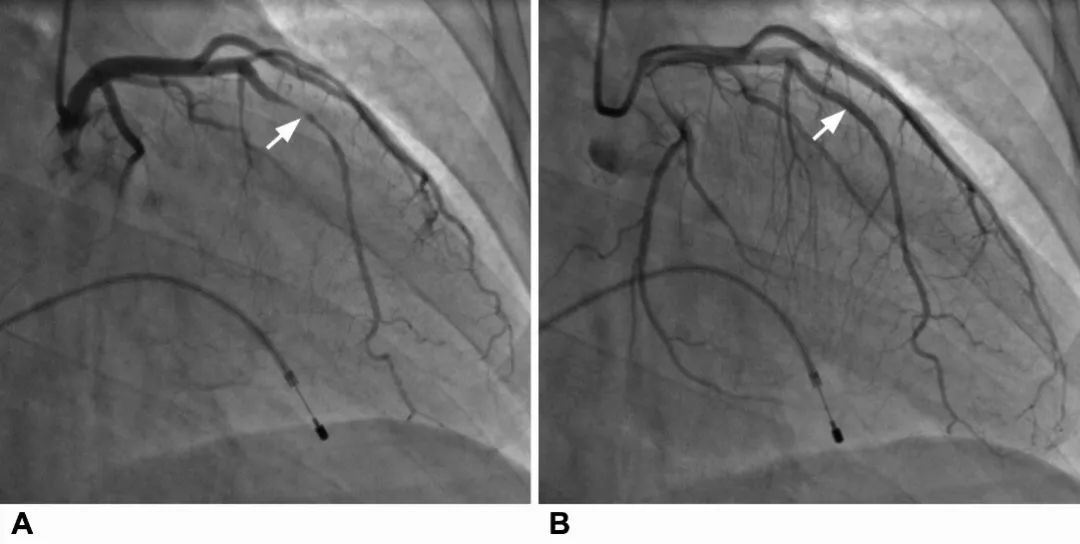

图3 A:心脏收缩冠状动脉前降支受到压缩,造影显示重度狭窄;B:舒张期狭窄消失

绝大多数心肌桥不会产生相关症状。正常心脏动脉血管会持续为心脏供血,心肌桥这一节段血管,在心动周期的收缩期会随着心脏收缩。由于心肌纤维收缩,心肌桥下的壁冠状动脉受到挤压,因此在冠状动脉造影时,可以发现该段走行于心肌桥下的壁冠状动脉在收缩期受到不同程度的挤压而呈现狭窄变细,而舒张期恢复正常,临床上将这种现象称为“挤奶现象( milking effect)”。